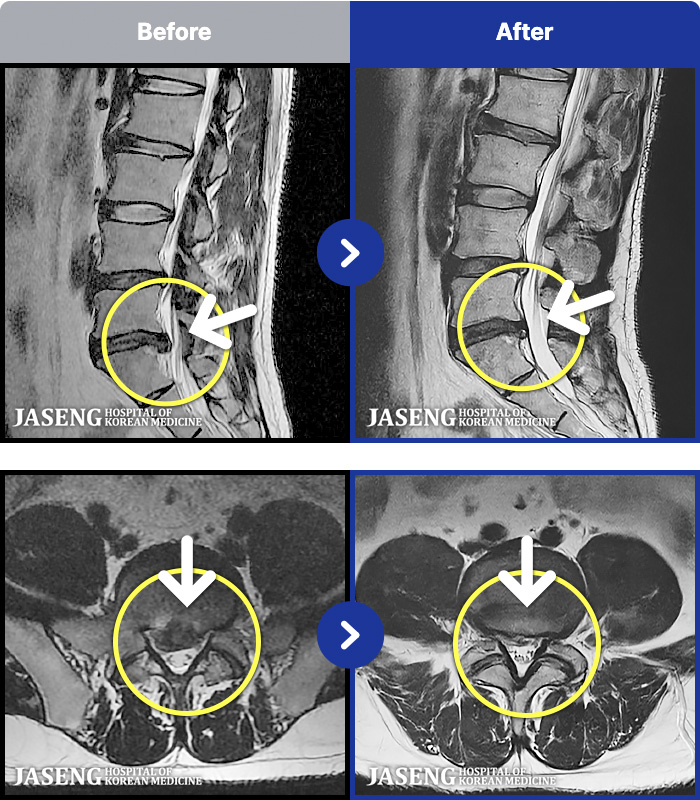

MRI ġ

MRI ũ ʸ Ȯϼ.